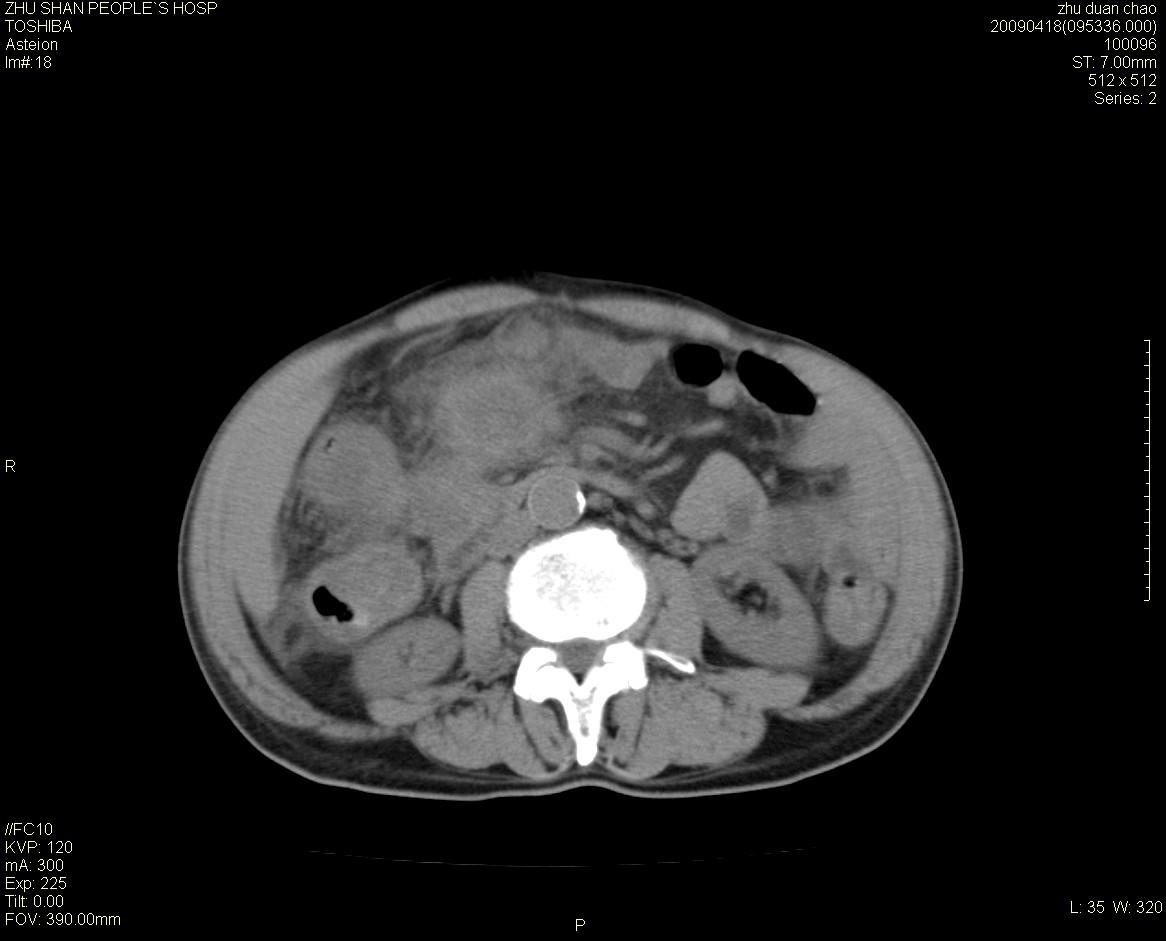

以下是引用余辉在2009-4-22 10:48:00的发言:[br]结肠肝曲附近肠段包块,病灶密度不均匀,周围肠系膜脂肪混浊,见多枚淋巴结肿大,考虑结肠癌可能性大,病灶累及范围较广建议进一步检查除外其他

以下是引用随光逐影在2009-4-22 11:57:00的发言:[br]考虑肠道肿瘤(间质瘤?)可能性大。

以下是引用ydx_74在2009-4-22 14:39:00的发言:[br]结肠癌周围侵犯可能,不能完全除外炎性病变